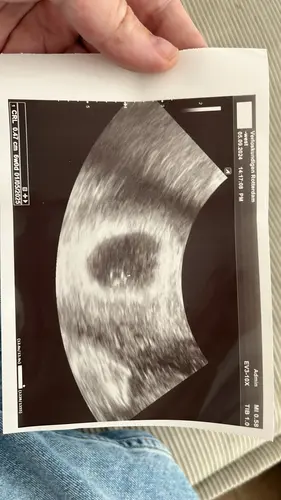

Eerste echo 6w 🥰 dacht zelf 6w5d maar terug gezet waardoor ik nu 1 mei ben ...